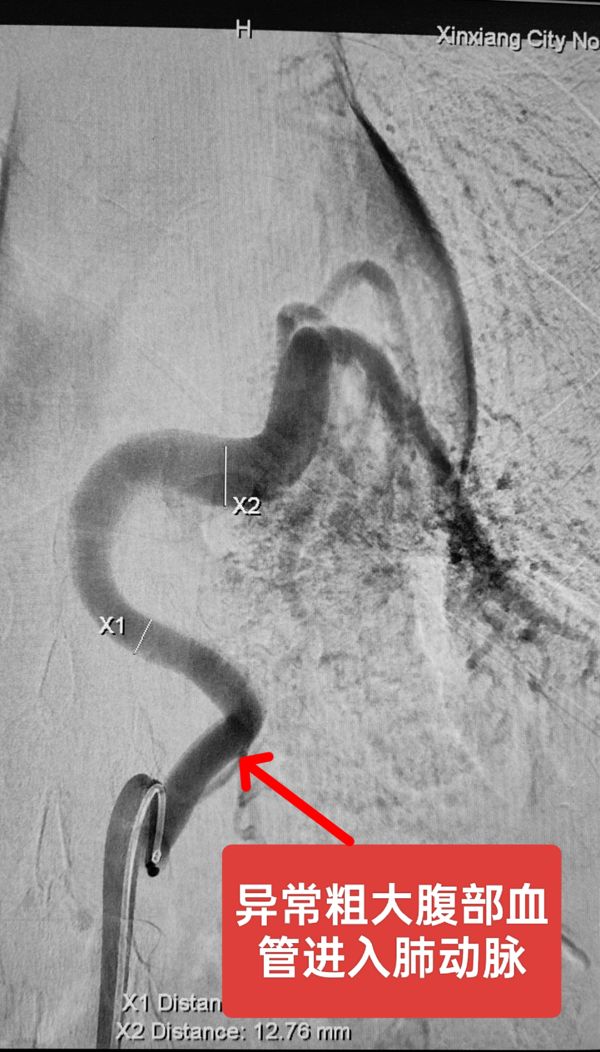

近日,我院介入科为一位少见直径约1cm腹腔干分支动脉参与肺部动静脉畸形并瘘口形成患者实施了可控弹簧圈加普通钢圈组合的“三明治”栓塞术,取得良好效果。该患者不明原因间断咯血十年余,王伟迪主任接诊后根据病史结合CTA影像表现制定了手术预案,为进一步降低患者手术费用,确定首先用可控弹簧圈栓塞瘘口以避免弹簧圈逃逸致大面积肺栓塞,之后用费用低廉普通钢圈闭塞近端粗大动脉。最终在介入手术室护技配合下手术获得成功。